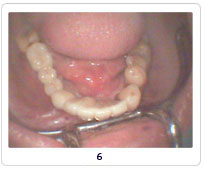

Implant Cases

Case 1   Case 2   Case 3   Case 4   Case 5   Case 6   Case 7   Case 8

Pictures Before And After Dental Implant India,Dental Implant Methods India,Types Of Materials Dental Implant Chennai India,X-ray Dental Surgery Goa India,Replacement Of Damaged Teeth Cochin India,Views Of Dental Treatment Procedure Delhi India,Dental Equipments Hyderabad India